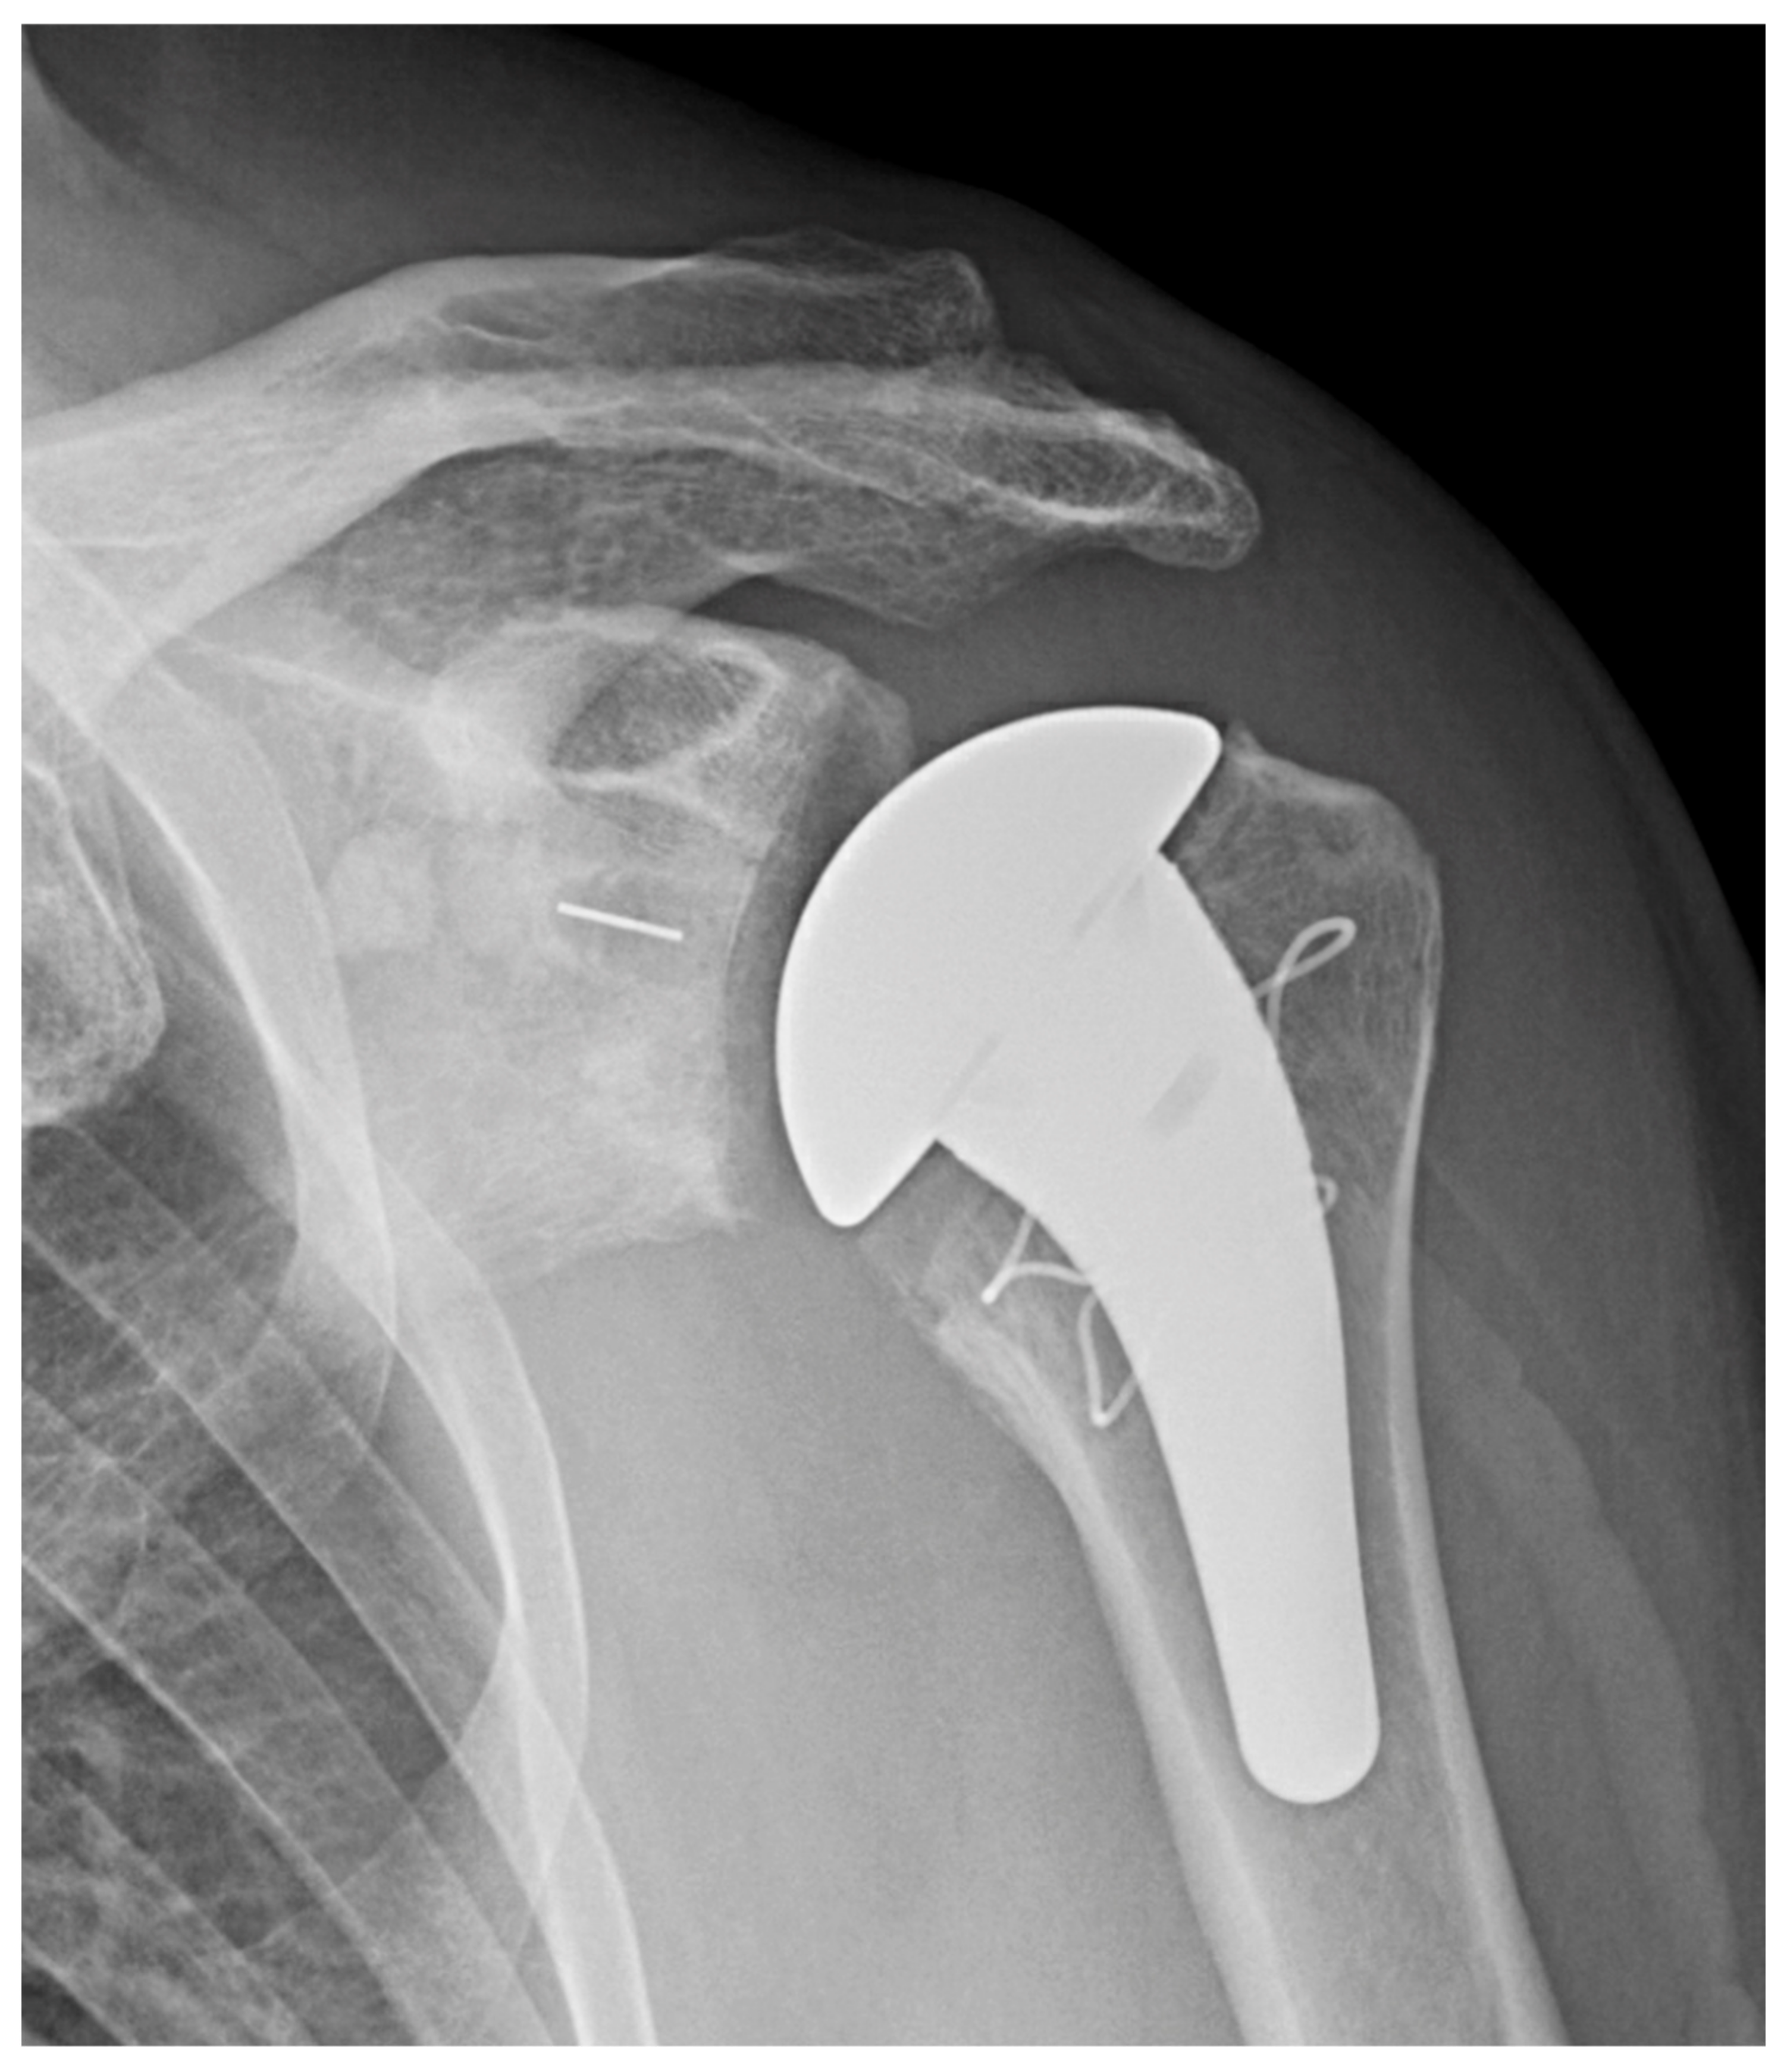

2.1.2. Short Stem Implants

3.2.1. Stemless Implants